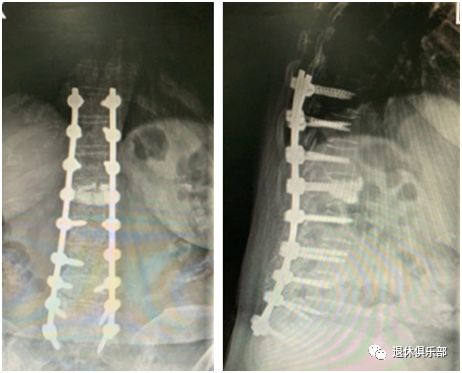

- 前些日子,葛阿姨去医院做了检查后被告知,她的脊椎严重侧弯,椎体发生了滑移,医生告诉她,如果再不治疗,可能下半辈子都得弯着腰度过了!这还不把葛阿姨“吓个半死”!所以,只能选择做一个六个多小时的手术,在脊